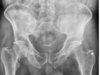

Masculino, 12 anos

Síndrome da sincondrose isquiopúbica assimétrica (Doença de Van Neck-Odelberg)

Variante da normalidade (em geral assintomático)

Crianças

Alargamento e radioluscência na sincondrose isquiopúbica, que simula neoplasias, infecção;